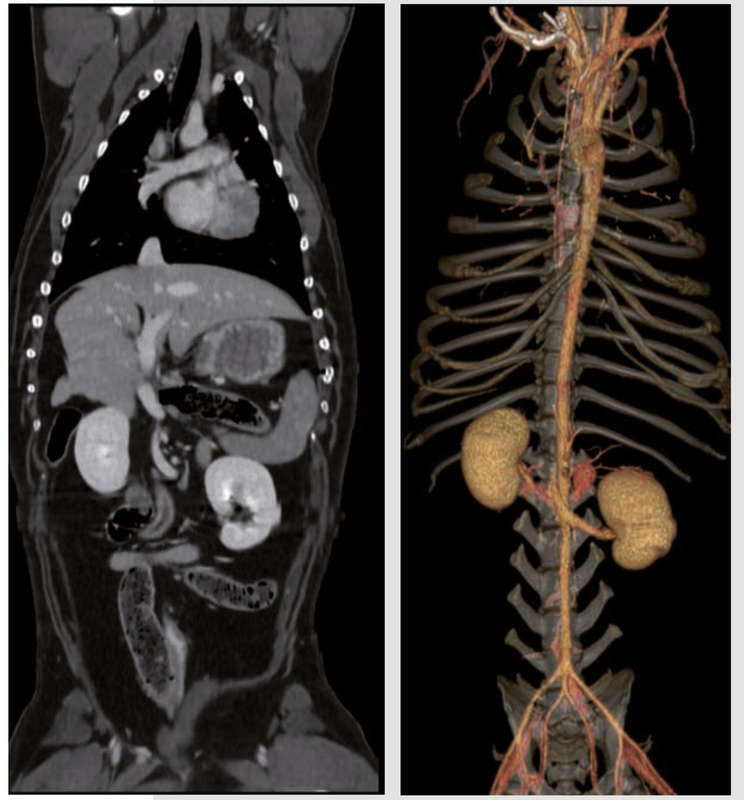

- Risoluzione spaziale di 18 lp/cm per consentire l’imaging di alta qualità e la visualizzazione dell’anatomia in 3D